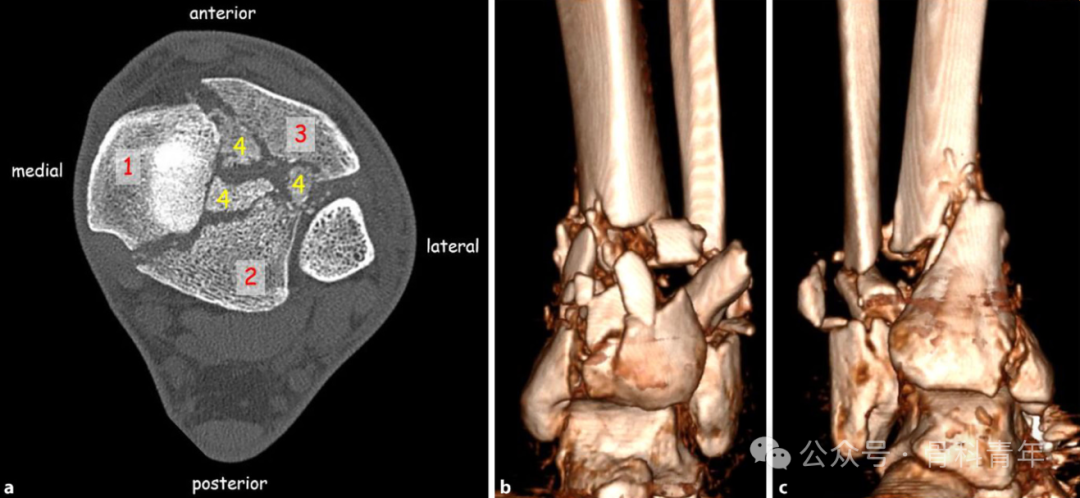

扫描(Scan):进行 CT 检查,包括三维重建;